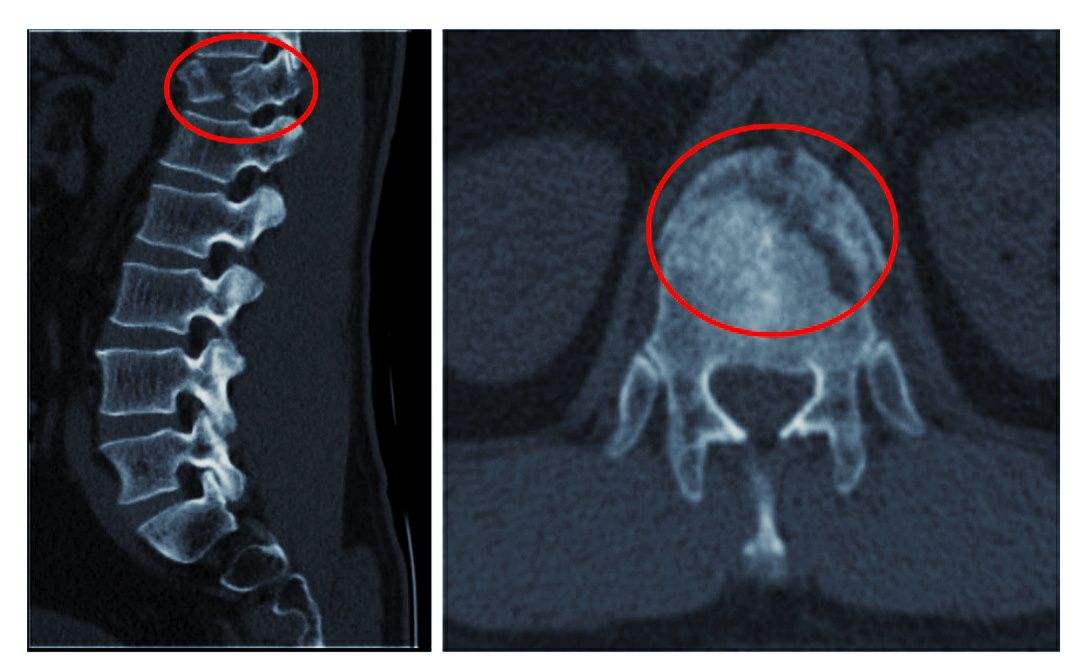

2、椎體緣、關(guān)節(jié)突、鉤椎關(guān)節(jié)骨贅形成

骨贅即骨質(zhì)增生俗稱為骨刺,是指骨關(guān)節(jié)邊緣上由于長(zhǎng)期慢性損傷引起瘢痕組織增生,天長(zhǎng)日久可產(chǎn)生鈣質(zhì)沉著變成骨質(zhì)而形成的。

由于椎間盤的退變,其后果必然導(dǎo)致頸椎生理曲線的改變,破壞了椎體間的平衡。久之,機(jī)體為了抵抗疼痛,使神經(jīng)免受刺激,建立新的平衡,而產(chǎn)生代償性骨贅,來(lái)穩(wěn)定脊柱。當(dāng)然骨贅形成的主要原因是急慢性損傷,骨贅的形態(tài)及部位與損傷的性質(zhì)等有關(guān),骨贅的大小與年齡有關(guān),與癥狀的輕重不一定成正比。若骨贅發(fā)生于椎間孔或椎管附近,可產(chǎn)生神經(jīng)根、椎動(dòng)脈或脊髓受壓癥狀。